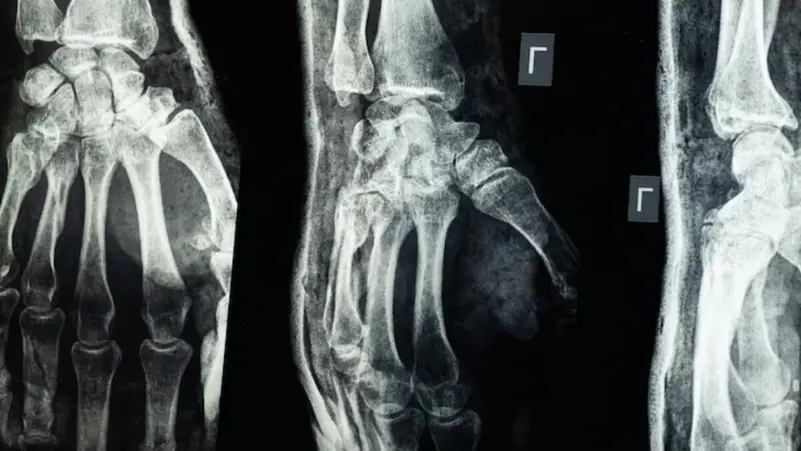

السوسنة - أعلن فريق بحثي في مقاطعة تشيجيانغ شرق الصين عن ابتكار طبي جديد يتمثل في "غراء عظمي" قادر على معالجة الكسور وتركيب الشظايا العظمية خلال ثلاث دقائق فقط في خطوة وُصفت بأنها اختراق علمي في عالم جراحة العظام.

ويتميز هذا الغراء بقدرته على التثبيت السريع والدقيق حتى في بيئة غنية بالدم، إلى جانب كونه يُمتص طبيعيًا من الجسم أثناء عملية الالتئام، ما يلغي الحاجة إلى عمليات جراحية لاحقة لإزالة المسامير أو الصفائح المعدنية.

وأكدت الاختبارات المعملية أن Bone-02 نجح في تحقيق نتائج جيدة من حيث السلامة والفعالية، حيث أُجريت إحدى العمليات في أقل من 180 ثانية، مقارنة بالوقت الطويل الذي تتطلبه الطرق التقليدية لزرع الصفائح والمسامير.

وبحسب التجارب، تمكن الغراء من تحقيق قوة ربط تفوق 400 رطل، وقوة قص تبلغ نحو 0.5 ميغاباسكال، وقوة ضغط تقارب 10 ميغاباسكال.

كما أظهرت التجارب على أكثر من 150 مريضًا نتائج ناجحة، ما يعزز احتمالية أن يصبح بديلاً للزراعات المعدنية التقليدية المستخدمة في تثبيت العظام، ويقلل من مخاطر العدوى.